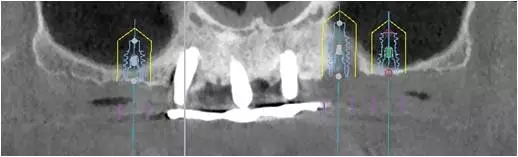

2、增加上頜種植體數(shù)量,分別與16、25、26植入3顆,行6顆種植體支撐的常規(guī)種植固定義齒修復(fù)(圖7)。16、25、26區(qū)剩余骨高度嚴(yán)重不足是該方案的不利方面,存在因需要上頜竇底提升手術(shù)所帶來(lái)的相應(yīng)手術(shù)風(fēng)險(xiǎn)。但是,上頜竇底提升術(shù)是一個(gè)成熟、可靠的技術(shù)方法,經(jīng)過(guò)與患者充分溝通,最終選擇了這一方案。

圖7